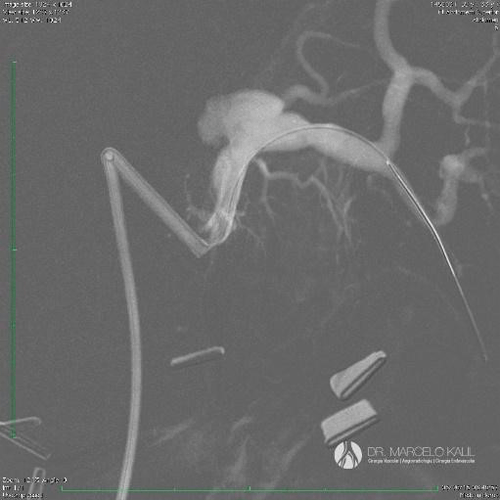

Dr. Marcelo Kalil

CRM 130623 | RQE 58565 | RQE 58565-1